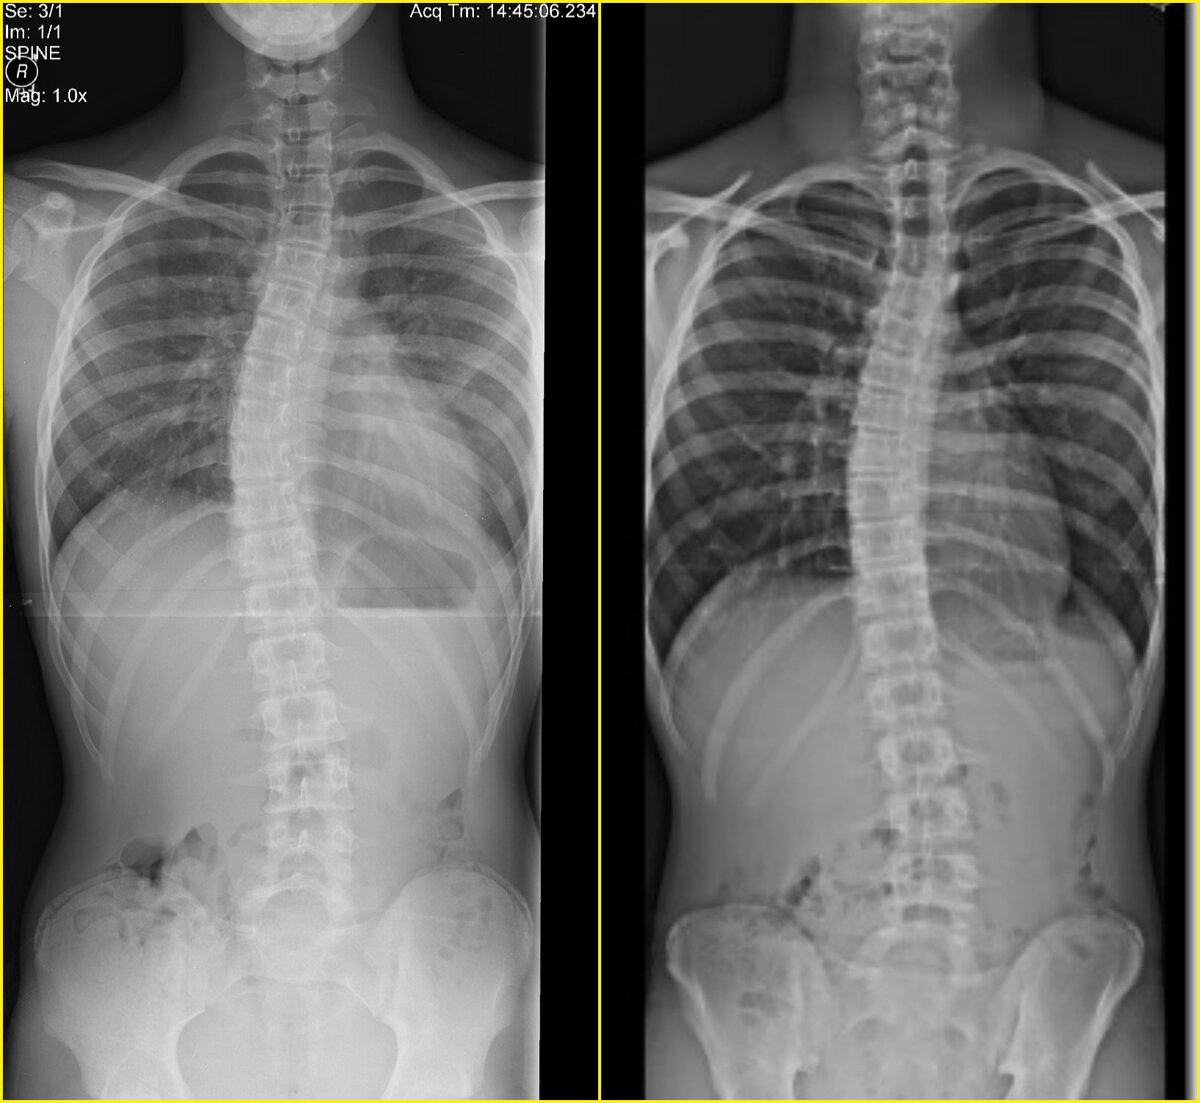

Сколиоз - это когда позвонки в разных комбинациях наклонены и повернуты. Когда это в грудном отделе - мы видим реберный горб с одной стороны спины. Но могут быть просто ребра разного размера, а сколиоза не быть. Потому этот диагноз ставится только по рентгеновскому снимку. Визуально на тестах мы можем только предположить его, но ни в коем случае не утверждать. Даже если видим змею из остистых отростков на спине - дуг может не оказаться, просто привычка так стоять или мышцы в не симметричном гипертонусе.

Почему без снимка нельзя лезть со своими упражнениями к человеку со сколиозом, чтобы тем же Шрот инвалидом его не сделать, если ребром ошибиться или углом. Это всегда точный индивидуальный алгоритм, потому исполняется только профессионалами. Иногда в несколько ступеней.